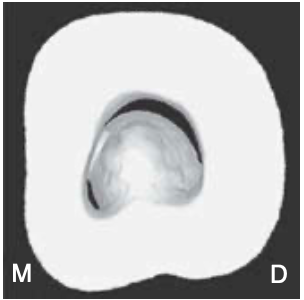

type III of pulpal floors

only one mesial, striplike dentin connection exists between the peninsula-like floor and the M wall

which separates the C-shaped groove into a small ML orifice and a large MB-D orifice

MB-D orifice was formed by the merging of the MB orifice and the D orifice (second most common)